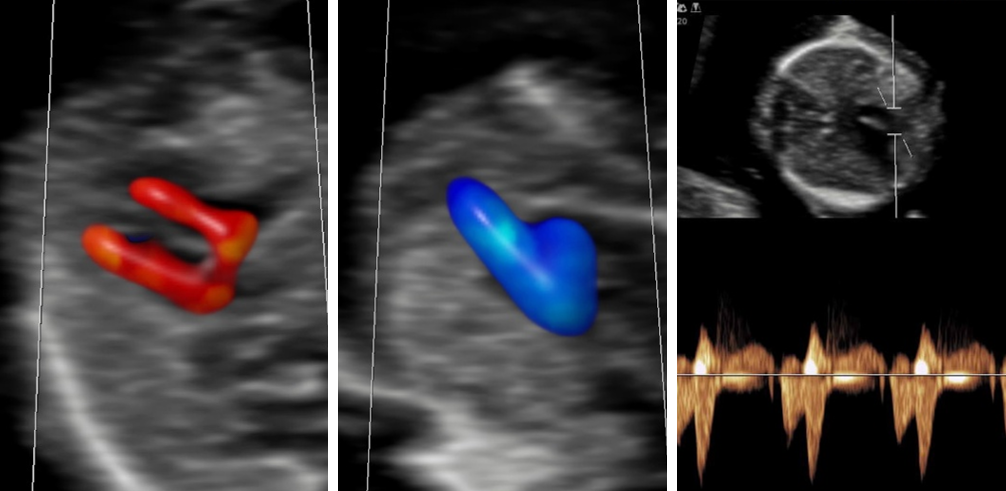

Doppler

Bei dieser Untersuchung messen wir die Durchblutung in der Nabelschnur und anderen Blutgefäßen, um die Versorgung Ihres Kindes zuverlässig einzuschätzen und zu überwachen. Je nach Fragestellung ist diese Untersuchung ab 11 SSW möglich.